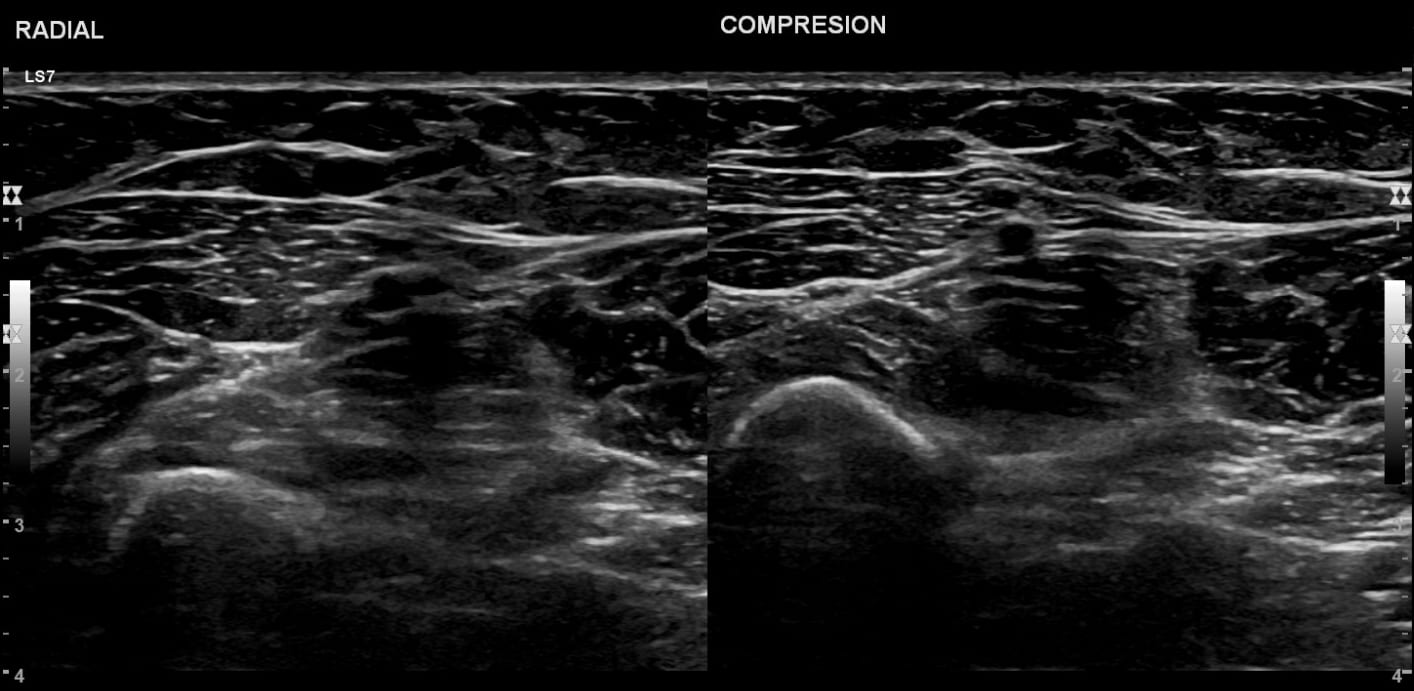

La ecografía Doppler de miembros superiores (MMSS) es un estudio de imagen no invasivo que combina ultrasonido convencional con la técnica Doppler para evaluar tanto la anatomía como el flujo sanguíneo de las arterias y venas de los brazos, desde el hombro hasta la mano.

- El ultrasonido genera imágenes de los vasos y tejidos.

- La modalidad Doppler mide la velocidad y dirección del flujo sanguíneo dentro de los vasos.

- Identificar trombosis venosa profunda (TVP) o tromboflebitis superficial.